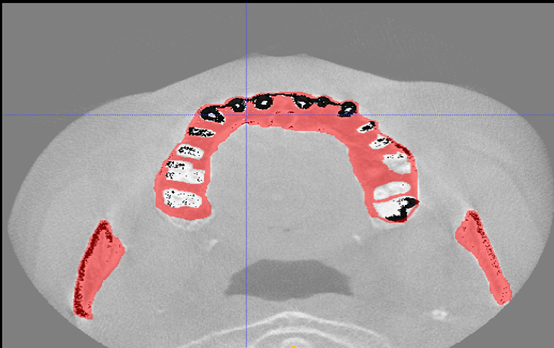

工作室团队成员目前包括李思博士、何远清老师、胡晨恺医生(南昌大学第二附属医院心内科主治医师)。另现有7名学生成员,包括20级1名、21级1名、22级5名,学生成员目前的研究主题包括:基于深度学习的冠脉造影狭窄智能检测技术研究(如图1所示);基于神经网络的智慧城市停车位检测技术研究(如图2所示);基于深度学习的口腔CT牙槽骨分割技术研究等(如图3所示)。

图3:基于深度学习的口腔CT牙槽骨分割技术研究